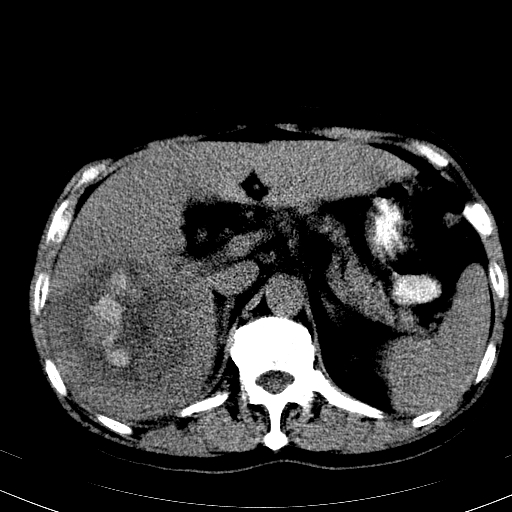

以下是引用卜一在2008-6-23 15:38:00的发言:[br]本例延时期的图象未扫完,单纯平扫 动脉期及门脉期特征分析:平扫低密度较大肿块,内见不规则出血灶,界限清楚。动脉期边缘结节样强化,门脉期病灶边缘进一步强化并范围明显缩小。因此考虑:血管瘤伴出血!

以下是引用深泽交通医院在2008-6-23 16:40:00的发言:[br]考虑肝癌伴出血.诊断依据:平扫瘤壁结节密度低于肝实质,动脉期壁结节明显强化,门脉期略低于肝实质密度[br]病灶有明显的假包膜,